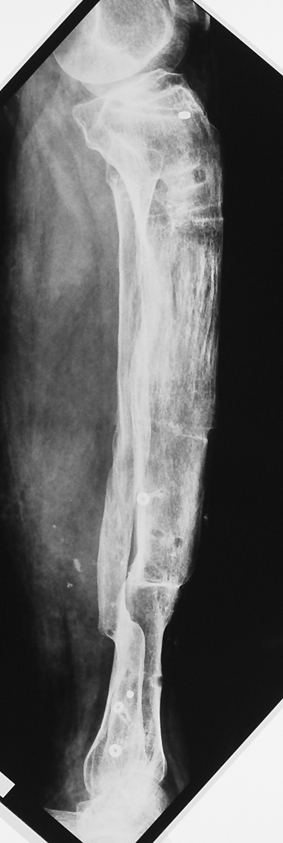

Kronik osteomiyelit, kemik ve yumuşak dokularda nekroza yol açar. Ölü kemik, patojen mikroorganizmalara ev sahipliği yapan bir nidus oluşturur. Konağın savunma sistemleri, mikroorganizmalarla baş etmek için sıklıkla optimal koşullarda değildir. Dolaşım bozukluğu yüzünden enfeksiyon bölgesine antibiyotikler yeterince ulaşamaz. Bu nedenle ölü dokuların ortamdan tamamen uzaklaştırılması gerekir (radikal debridman).

Uygun radikal debridman tüm nekrotik kemik ve yumuşak dokuların çıkartılmasını gerektirir, ve sıklıkla uzuvda instabiliteye neden olur. Kalan kemik ve yumuşak doku defektinin bir şekilde fiksasyonu ve rekonstrüksiyonu gereklidir. İlizarov’un ortaya koyduğu distraksiyon osteogenezi yöntemi, kaynamanın elde edilmesi, deformitenin düzeltilmesi, bacak boy eşitsizliğinin giderilmesi ve segmental defektlerin rekonstrükte edilmesi için başarıyla kullanılmaktadır.